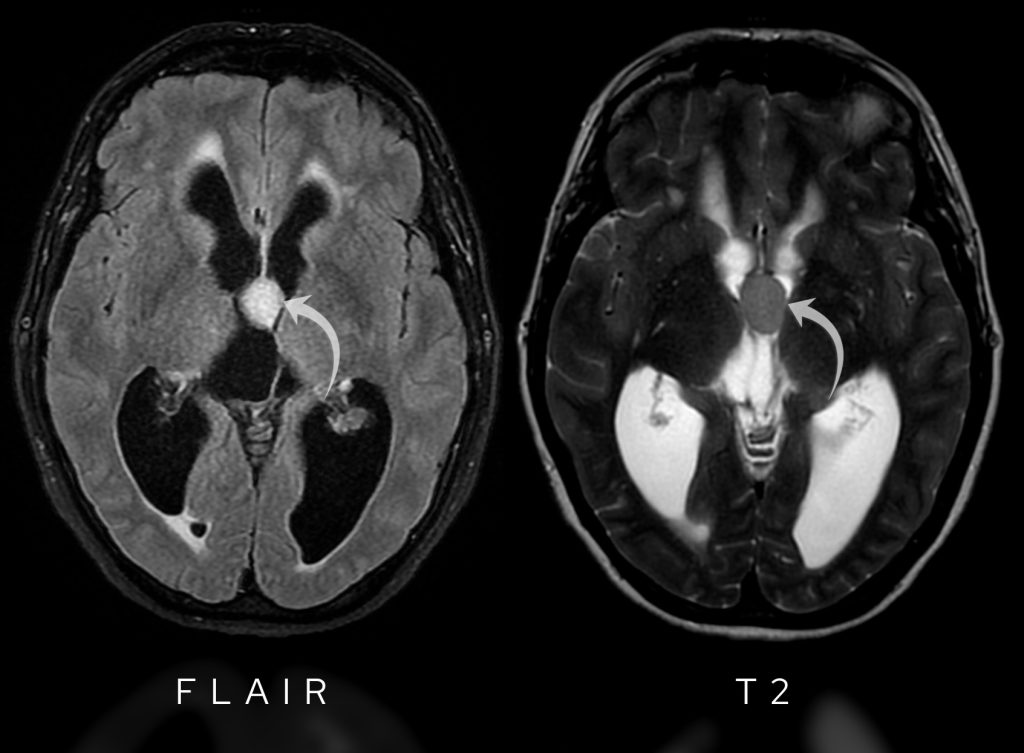

- FLAIR: The lesion is bright, indicating abnormal tissue.

- T2-weighted: It’s not as bright as CSF but slightly hyperintense compared to grey and white matter.

FLAIR images show hyperintensity within the lesion whilst T2-weighted images show the lesion is hypointense to CSF.